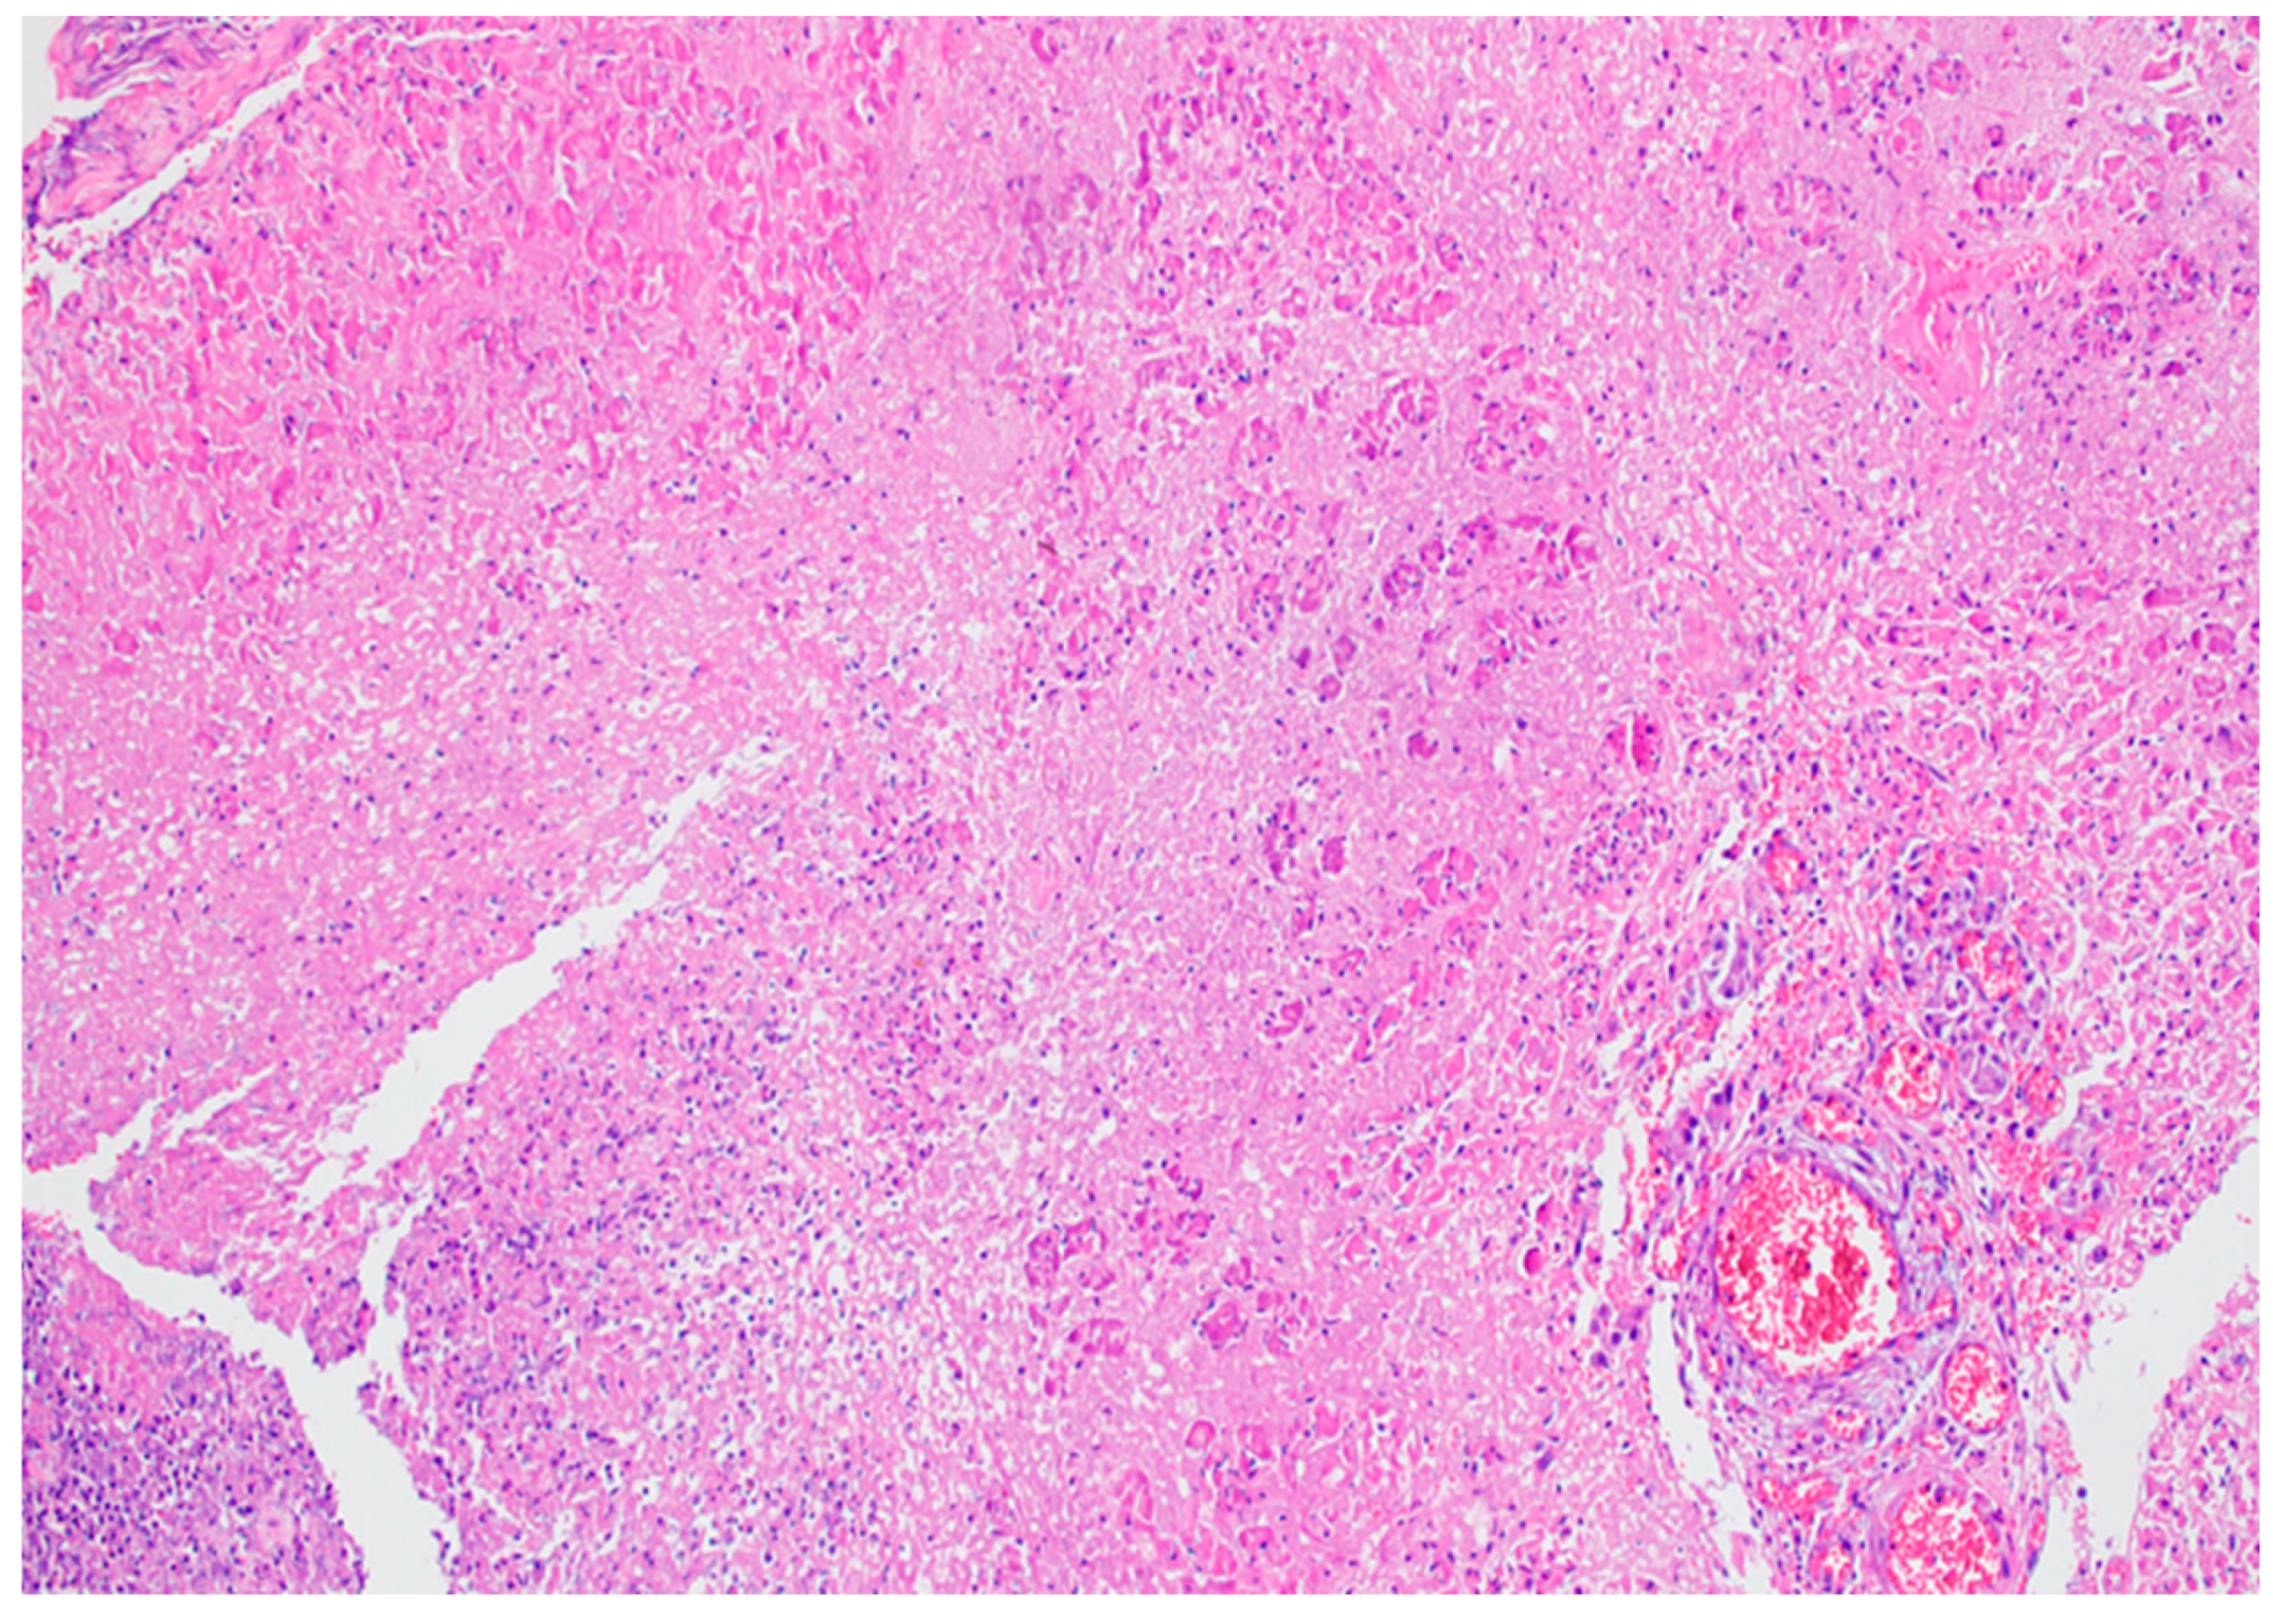

- Centro-acinar cells—delimiting the lumen together with acinar cells; they are small, flattened, or cuboidal in shape; the cytoplasm is pale, and the nucleus is oval; these cells are considered reserve cells for acinar and ductal cells (see Figure 4a).

- Intralobular ducts—represented by intercalated ducts that continue the lumen of the acini and are delimited by simple cuboidal epithelium; intercalated ducts fuse to form proper intralobular ducts, which are larger and delimited by simple cuboidal or columnar epithelium; around these ducts, a loose connective stroma can be observed, with numerous reticulin fibers, yet quantitatively reduced overall; unlike major salivary glands, the exocrine pancreas does not have striated ducts (see Figure 4a,b).

- Interlobular ducts—located in connective trabeculae; they have a wide lumen and are delimited by simple columnar epithelium; they are surrounded by well-represented, dense, irregular connective tissue, which contains fibroblasts and myofibroblasts (see Figure 5).